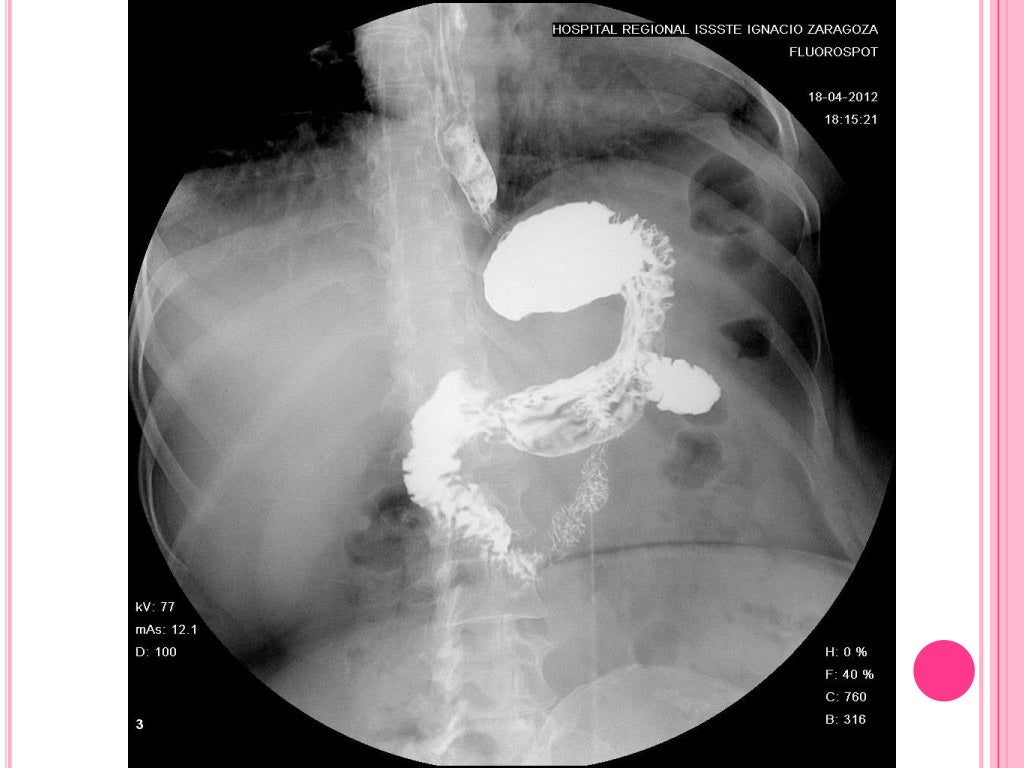

Nos podéis encontrar de lunes a viernes (sábados, domingos y festivos cerrado) en: GEMA Centro Médico de Especialidades I: C/ Nou, 13-15 - Mataró · Horario: de 8:00 a 13:30 y 15:30 a 21:00h GEMA Centro Médico de Especialidades II: C/ Pizarro, 27 - Mataró · Horario: de 8:00 a 20:30h GEMA Rehabilitación y Fisioterapia: C/ José M. Torrijos, 55 - Mataró · Horario: de 08:00 a 20:30h. El tránsito esofagogastroduodenal, conocido en inglés como "upper gastrointestinal (GI) series", usa rayos X para ayudar a diagnosticar problemas del tracto gastrointestinal superior, que comprende el esófago, el estómago y el duodeno. El duodeno es la primera parte del intestino delgado. Estómago. Duodeno.

pruebas radiologicas:Maquetación 1. ESTUDIO ESÓFAGO-GASTRODUODENAL. TRÁNSITO INTESTINAL. ¿QUÉ ES UN ESTUDIO ESÓFAGO-GASTRODUODENAL O UN TRÁNSITO INTESTINAL? El estudio esófago-gastroduodenal es una prueba diagnóstica con contraste que permite obtener imágenes del esófago, el estómago y el intestino delgado.. Cuando la porción del tracto digestivo estudiado corresponde al intestino delgado (duodeno, yeyuno e ileon) hablamos de tránsito intestinal. Cuando la porción del tracto digestivo estudiado corresponde al esófago, estómago y primera porción de intestino delgado hablamos de tránsito esofagogastroduodenal.